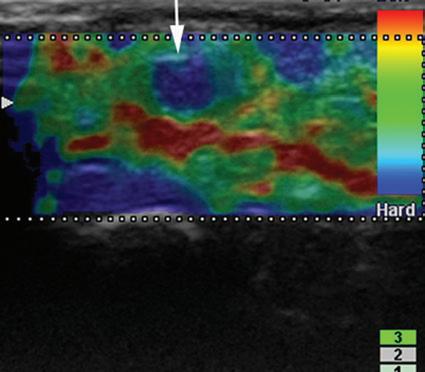

is fusion imaging, in which real-time ultrasound imaging can be superimposed on computed tomography (CT) or MRI; this has been used to assist with needle guidance for sacroiliac joint injections.17 One last technique is sonoelastography, which is used to assess the elastic properties of tissue. The three types of sonoelastography include compression elastography (using manual compression), shear wave elastography (using a directional shear wave), and transient elastography (using a short pulse).18 With compression elastography, manual compression of tissue produces strain or displacement within the tissue. Displacement is less when tissue is hard; it is displayed as blue on the ultrasound image, whereas soft tissue is displayed as red (Fig. 1.27). With regard to musculoskeletal applications, normal tendons appear as blue, whereas areas of tendinopathy, such as of the Achilles tendon or common extensor tendon of the elbow, appear as red.16,19-22 With shear wave and transient elastography, the velocity of the shear wave is measured to determine elasticity and has the advantage of less operator dependence and ability to produce qualitative and quantitative information.18,23

area below white arrow). Note that hard tissues are displayed in blue and soft tissues in red. (Courtesy

Michigan.)